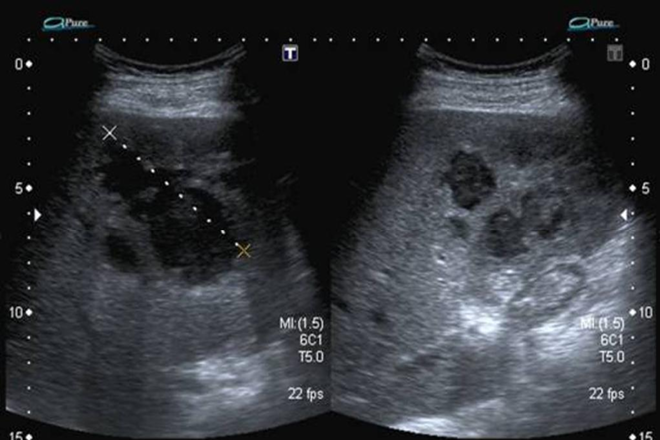

Vesícula biliar

Vesícula biliar La vesícula biliar es un receptáculo músculo-membranoso en forma de pera, que mide aproximadamente 8 a 10 cm de longitud por 3,5 a 4 cm de diámetro. Se encuentra alojada en la fosilla cística, ubicada en la cara inferior del hígado, por fuera del lóbulo cuadrado y en